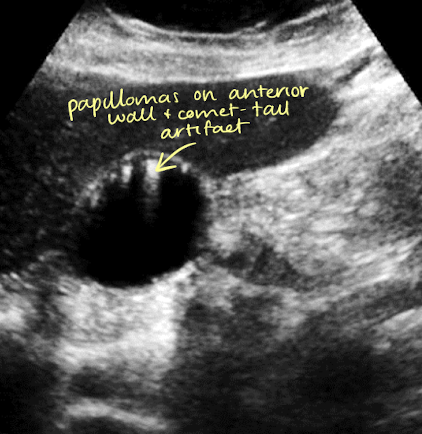

adenomyomatosis

cholesterol crystals that settle within the Rokitansky-Aschoff sinuses of GB wall

mucosal hyperplasia (thickening of muscular layer of GB wall); papillomas occur

SONO: thickening of wall with internal cystic spaces

echogenic foci on wall with “comet tail” artifact

??